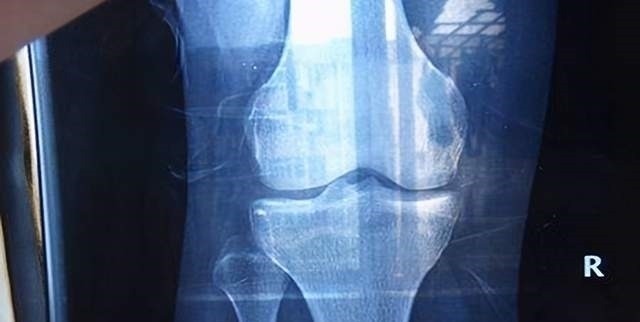

除了让孩子吃得好、睡得好、玩的好,家长还需要提防孩子“性早熟”。因为“性早熟”对孩子的直接影响就是“长不高”。即使在孩子的发育初期会因为“性早熟”比同龄人长得更快,但是这种短暂的身高优势后会使他们的发育在后期停滞不前,最终比同龄人矮5-10mm。因为人的骨骼发育需要钙,而性早熟的孩子钙储备并不多,并且性早熟会加速骨骼骨骺线闭合,所以孩子会暂停长个。